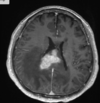

Doença de Creutzfeldt Jacob

Variante Creutzfeldt

Qual o padrão da imagem na DCJ?

Hiperintensidade T2 e especialmente na difusão em regiões de núcleos da base, tálamos e córtex. O hipersinal no pulvinar do tálamo e no núcleo dorsomedial é descrito como sinal do taco de hockey. Lobos mais frequentemente envolvidos são frontal e parietal.

Qual o padrão da doença de creutzfeldt jacob?

Lesões que podem ser bilaterais e simétricas, com hipersinal em T2 nos nucleos da base: estriado bilateral, tálamo (sinal do pulvinar e do taco de hóckey), córtex e substância branca; A restrição à difusão é o sinal mais sensível;